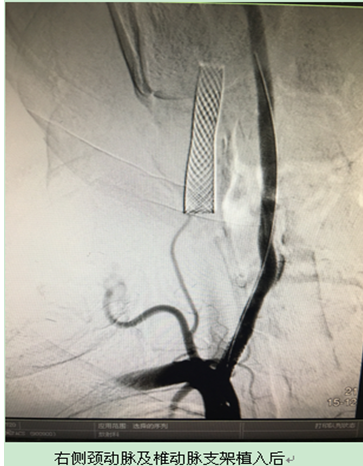

考虑到患者颈部动脉病变复杂,同时又合并冠心病、高血压等疾病,血管外科罗文军教授、孙建明主任、陈以宽副主任及血管外科医护团队反复详细讨论手术方案:决定分期分步、开放手术联合介入支架植入的综合手术原则。为避免发生术后大脑高灌注、脑出血,在积极的术前准备后,陈以宽教授、祁小桐博士,罗海龙博士首先在局部麻醉下成功为患者进行了右侧颈内动脉支架植入术,术后两天再次在局部麻醉下行双侧椎动脉支架植入术,后又在手术室行开放左侧颈动脉内膜剥脱术(CEA)。7天后复查超声显示颈部动脉血流通畅,患者顺利出院。